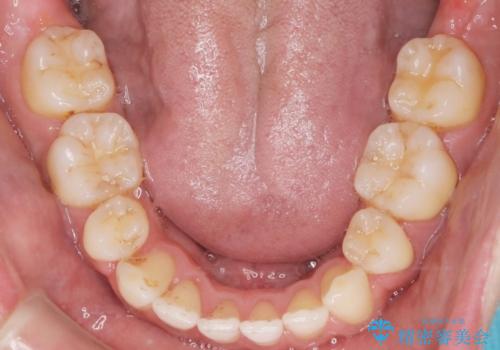

- 上の前歯の隙間と口元を下げたとのことで来院されました。

上顎正中離開と、口唇の突出感がありました。

上下左右の歯を1本ずつ抜歯しして、上顎の前歯を後方に移動させるのと、正中の隙間を閉じる計画としました。